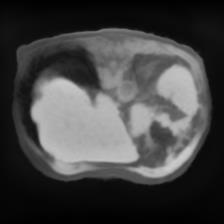

In clinical practice, well-aligned multi-modal images, such as Magnetic Resonance (MR) and Computed Tomography (CT), together can provide complementary information for image-guided therapies. Multi-modal image registration is essential for the accurate alignment of these multi-modal images. However, it remains a very challenging task due to complicated and unknown spatial correspondence between different modalities. In this paper, we propose a novel translation-based unsupervised deformable image registration approach to convert the multi-modal registration problem to a mono-modal one. Specifically, our approach incorporates a discriminator-free translation network to facilitate the training of the registration network and a patchwise contrastive loss to encourage the translation network to preserve object shapes. Furthermore, we propose to replace an adversarial loss, that is widely used in previous multi-modal image registration methods, with a pixel loss in order to integrate the output of translation into the target modality. This leads to an unsupervised method requiring no ground-truth deformation or pairs of aligned images for training. We evaluate four variants of our approach on the public Learn2Reg 2021 datasets \cite{hering2021learn2reg}. The experimental results demonstrate that the proposed architecture achieves state-of-the-art performance. Our code is available at https://github.com/heyblackC/DFMIR.